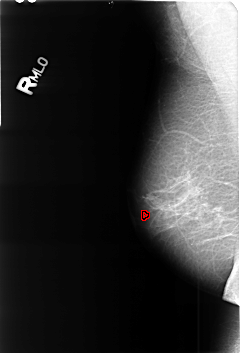

B_3447_1.RIGHT_MLO

FILE: B_3447_1.RIGHT_MLO.OVERLAY

TOTAL_ABNORMALITIES 1

ABNORMALITY 1

LESION_TYPE CALCIFICATION TYPE SKIN-COARSE-ROUND_AND_REGULAR DISTRIBUTION N/A

ASSESSMENT 2

SUBTLETY 3

PATHOLOGY BENIGN_WITHOUT_CALLBACK

TOTAL_OUTLINES 1

BOUNDARY